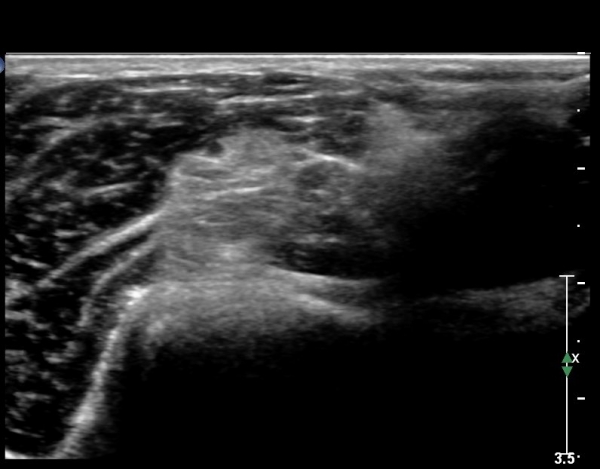

ÃÊÀ½ÆÄ ¼Ò°ß

ÆÈ²ÞÄ¡ ¾Õ Ȳ´Ü¸é °Ë»ç¿¡¼­ ¼ÒµÎ Àü¸é¿¡ ÀÌÁú¼º °í¿¡ÄÚ(heterogenous htperechoic)ÀÇ Á¾±«(mass)°¡

Èİñ°£½Å°æÀ» Ç¥ÃþÀ¸·Î ÀüÀ§½ÃŰ´Â ¾ç»óÀ¸·Î °üÂûµÊ(»çÁø 1).